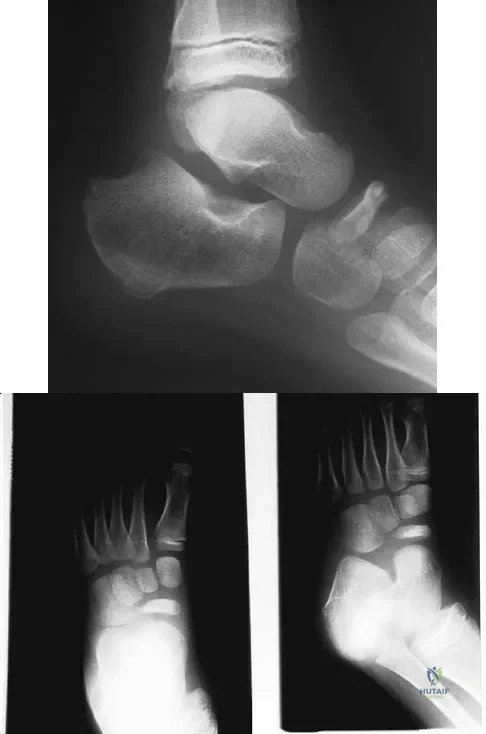

Question 27

A 26-year-old ballet dancer reports posterolateral ankle pain, especially with maximal plantar flexion. Examination reveals maximal tenderness just posterior to the lateral malleolus, and symptoms are heightened with forced passive plantar flexion. Radiographs are shown in Figures 42a and 42b. What is the most likely cause of the patient's symptoms?

Explanation

Question 28

A 5-year-old boy has had midfoot pain with activity for the past 3 months. He has no pain at rest. Radiographs are shown in Figures 29a and 29b. Management should consist of

Explanation